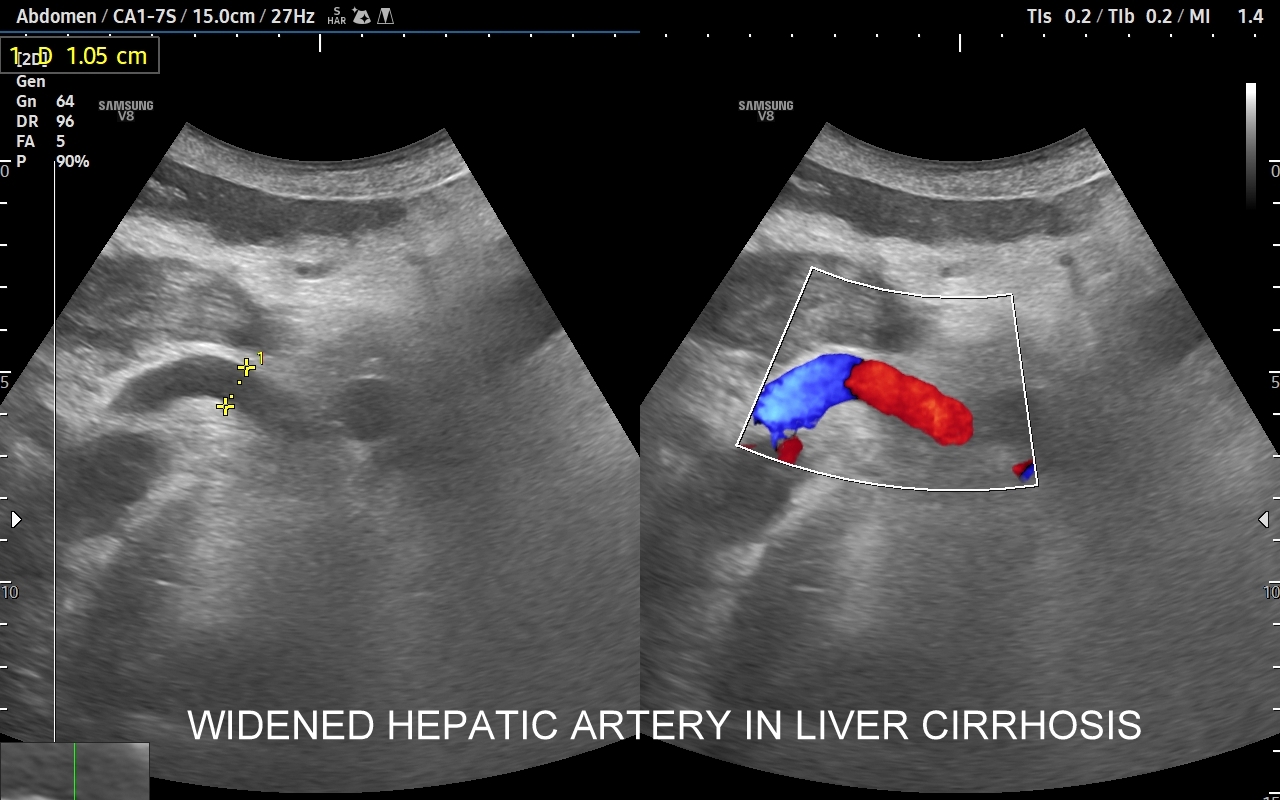

Wątroba posiada unaczynienie różnego typu, a każde o swojej indywidualnej charakterystyce. Są to unaczynienie tętnicze, unaczynienie wrotne (żyła wrotna i jej dopływy z narządów jamy brzusznej), odpływ żylny poprzez żyły wątrobowe. W USG Doppler przepływów wątrobowych bada się każdy z tych układów.

Badanie USG Doppler układu wrotnego wątroby łącznie ze standardową oceną morfologii wątroby i śledziony wykonywane jest najczęściej w ramach diagnostyki nadciśnienia wrotnego, czyli podwyższonego ciśnienia krwi w żyle wrotnej, które może być przyczyną zagrażających życiu żylaków przełyku. Badanie dopplerowskie wątroby uzupełnia również diagnostykę marskości wątroby oraz służy wykrywaniu takich patologii jak zakrzepica w żyle wrotnej i jej dopływach, zakrzepica w żyłach wątrobowych, czy rozprzestrzeniające się nowotwory w naczyniach wątroby.

Wskazania do przeprowadzenia oceny naczyń wątroby (USG Doppler przepływy wątrobowe) w postaci badania Doppler są szerokie, a obejmują przewlekłe oraz przebyte choroby wątroby, nadużywanie alkoholu, ciężkie zatrucia chemikaliami i grzybami, zapalenia i marskość wątroby, stan po transplantacji wątroby, a także stwierdzoną chorobę nowotworową w obrębie jamy brzusznej oraz objawy w postaci bólów czy dyskomfortu brzucha. W razie potrzeby kompleksowej oceny wątroby oprócz badania Doppler warto jednocześnie przeprowadzić elastografię 2D-SWE najoptymalniej w ramach kompleksowego tzw. multiparametrycznego badania USG/ MPUS jamy brzusznej >